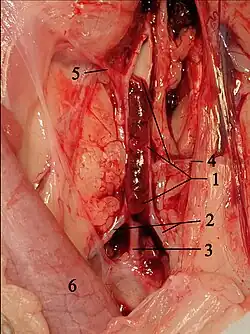

Thrombus in the terminal branch of the aorta in a cat. 1 opened aorta with thrombus, 2 external iliac arteries, 3 common trunk of both internal iliac arteries, 4 circumflex ilium profunda, 5 mesenteric caudal artery, 6 descending colon. circumflexa ilium profunda, 5 A. mesenterica caudalis, 6 Colon descendens